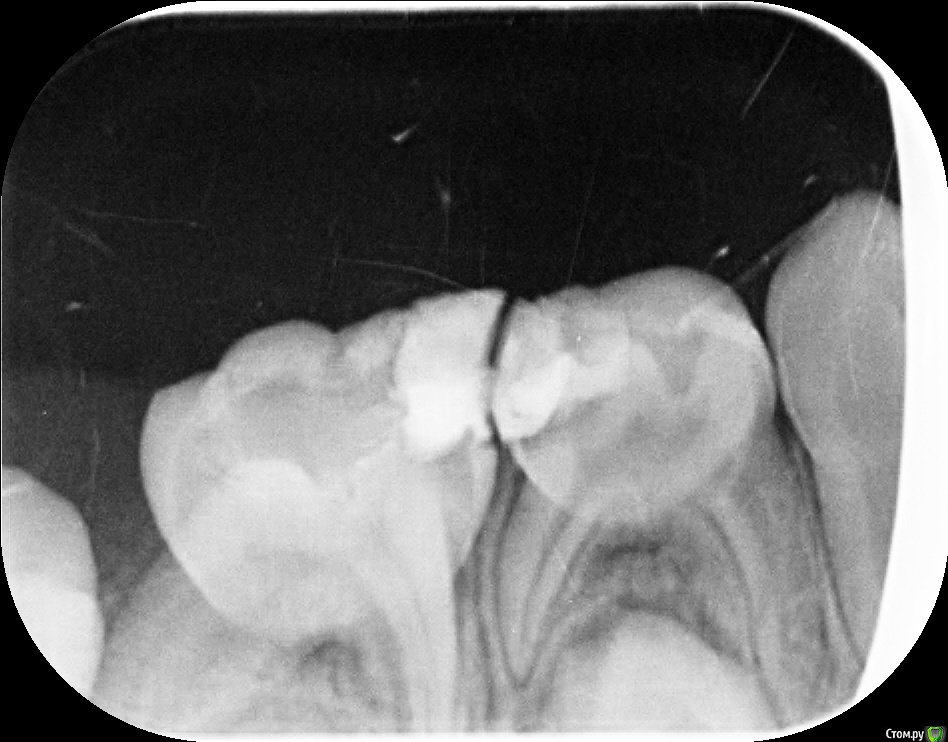

Zenden Опубликовано 2 ноября, 2019 Поделиться Опубликовано 2 ноября, 2019 (изменено) Добрый день, ребенку 5.5 лет, жалуется на зубную боль нижнего 4 или скорее 5 зуба справа, но не можем понять точно какой именно зуб болит, и почему он вообще разболелся если на обоих зубах уже есть пломбы.В клинике, где делали снимки, врач предположила про 5-ку, предложила убрать пломбу и пролечивать каналы. Хочется услышать еще мнений что делать, спасибо. если это важно, то перед зубной болью ребенок перенес ОРВИ Изменено 2 ноября, 2019 пользователем Zenden Ссылка на комментарий

red_butler Опубликовано 2 ноября, 2019 Поделиться Опубликовано 2 ноября, 2019 Оба лечить Ссылка на комментарий

Zenden Опубликовано 22 ноября, 2019 Автор Поделиться Опубликовано 22 ноября, 2019 Тему можно закрывать? да, 5-ку в итоге удалили Ссылка на комментарий

red_butler Опубликовано 22 ноября, 2019 Поделиться Опубликовано 22 ноября, 2019 да, 5-ку в итоге удалилиТеперь наблюдайтесь у ортодонта Ссылка на комментарий